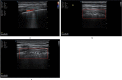

A novel coronavirus (2019-nCoV) was identified as the cause of a cluster of pneumonia in Wuhan, China, at the end of 2019. Since then more than eight million confirmed cases of coronavirus disease 2019 (COVID-19) have been reported around the globe. The current gold standard for etiologic diagnosis is reverse transcription-polymerase chain reaction analysis of respiratory-tract specimens, but the test has a high false-negative rate owing to both nasopharyngeal swab sampling error and viral burden. Hence diagnostic imaging has emerged as a fundamental component of current management of COVID-19. Currently, high-resolution computed tomography is the main imaging tool for primary diagnosis and evaluation of disease severity in patients. Lung ultrasound (LUS) imaging has become a safe bedside imaging alternative that does not expose the patient to radiation and minimizes the risk of contamination. Although the number of studies to date is limited, LUS findings have demonstrated high diagnostic sensitivity and accuracy, comparable with those of chest computed tomography scans. In this note we review the current state of the art of LUS in evaluating pulmonary changes induced by COVID-19. The goal is to identify characteristic sonographic findings most suited for the diagnosis of COVID-19 pneumonia infections.